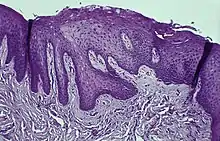

Immunohistochemical staining with FXIIIa [9] antibody disclosed a population of reactive spindle- or stellate-shaped cells[10] in 11 of 15 cases, located in connective tissue papillae and in a few cases also distributed throughout the lesion. The FXIIIa-stained cells appeared together with the frequently observed stellate, "young" occasionally multinucleated fibroblastic cells observed in more than 50% of patients aged 10–69 years. It is likely that FXIIIA-expressing "mucosal dendrocytes" are pathologically involved in some way.[11][12][13]